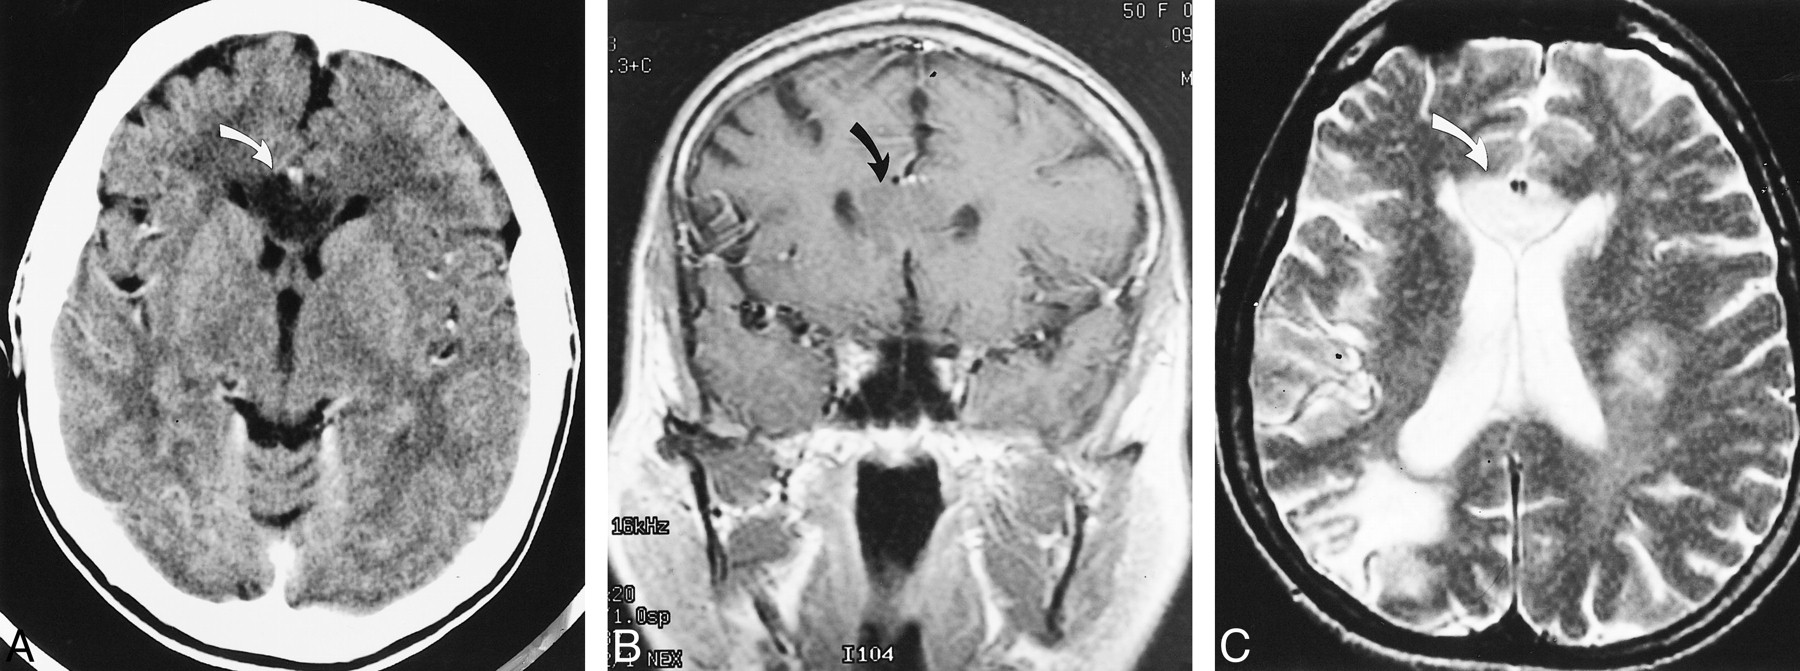

A 50-year-old woman with a past medical history significant for insulin-dependent diabetes mellitus and hypertension presented with two episodes of transient left-sided weakness. Non-contrast CT upon admission showed a 2-cm low-density lesion within the genu of the corpus callosum. Old infarcts in the right parietal and posterior frontal regions were also noted. Follow-up contrast-enhanced CT (Fig 1A) 2 days later again showed a non-enhancing lesion within the corpus callosum. There was mass effect on the frontal horns of the lateral ventricles. Contrast-enhanced T1-weighted MR imaging (Fig 1B) revealed an expansile, hypointense lesion within the body and genu of the corpus callosum that was hyperintense on the T2-weighted images (Fig 1C) and attributed to be the cause of the patient's symptoms. No abnormal enhancement was seen. Based on the clinical and radiologic findings, a low-grade glioma was considered, and a biopsy was performed 12 days after the initial CT examination. The results of the biopsy confirmed an infarct.

Case 1. Axial postcontrast CT image (A) and coronal postcontrast T1-weighted image (B) (480/20/1 [TR/TE/excitations]) show a non-enhancing lesion within both sides of the genu (curved arrow) of the corpus callosum with mass effect on the frontal horns. Axial T2-weighted image (C) (2500/105/1) shows corresponding high signal intensity within the genu of the corpus callosum (curved arrow), crossing the midline. An old infarct is noted within the right posterior border zone and scattered foci of T2 signal abnormality are seen in the left frontal and parietal regions. A biopsy of the lesion was obtained, confirming an infarct